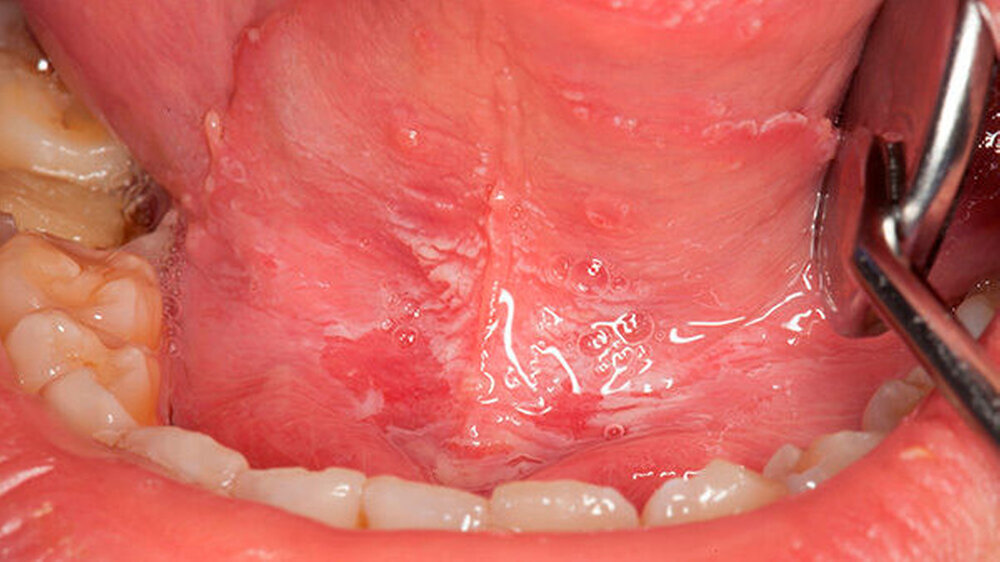

Nach einer aktuellen Studie der University of California, LA, über diehierberichtet wird, enthalten E-Zigaretten mehr schädliche Substanzen und Nanopartikel als für die Mundflora gut ist. Laut den Studienautoren beeinträchtigen die schädlichen Dämpfe den natürlichen Abwehrmechanismus im Mund und sorgen dafür, dass die oberste Schicht der Hautzellen in der Mundhöhle abgetötet wird.